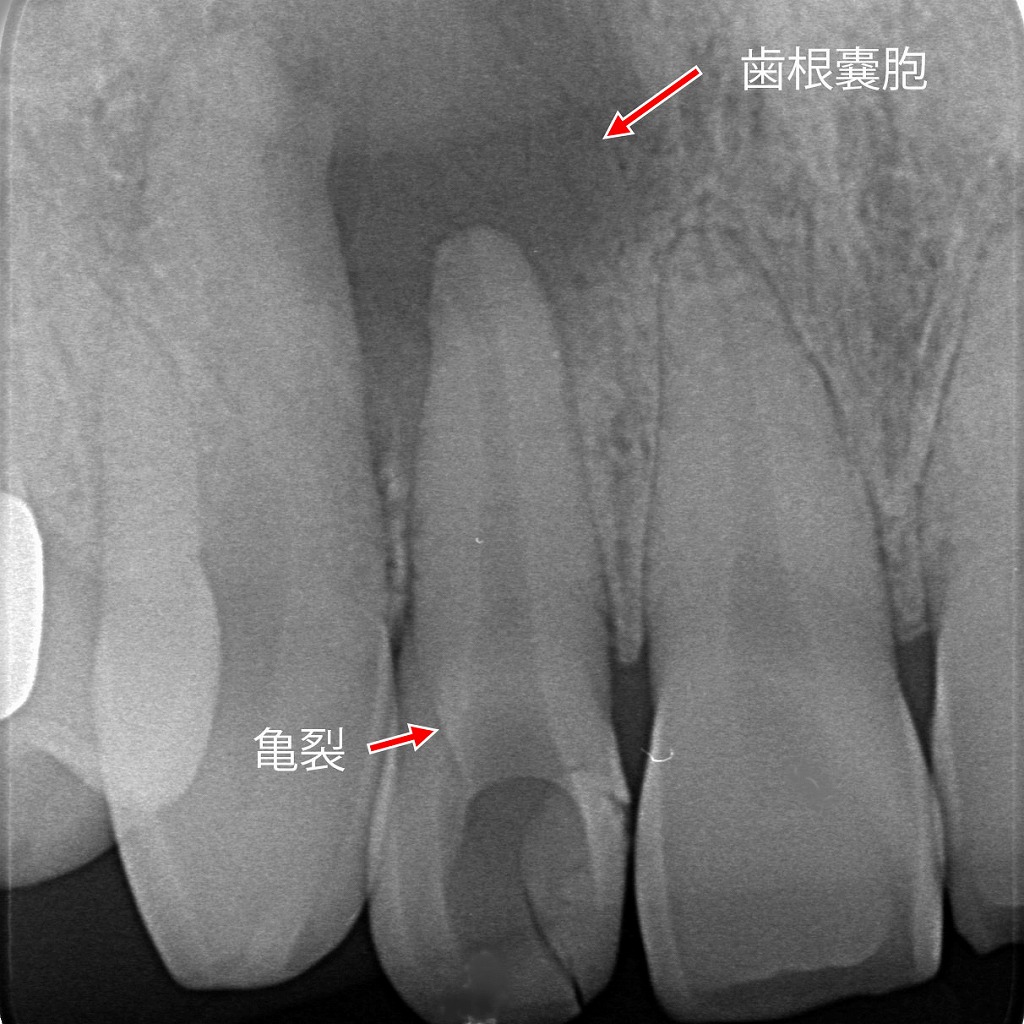

- 6.1.1. レントゲン診断-歯根まで及ぶ深い亀裂と歯根嚢胞 ― 保存が困難と判断された症例

レントゲン診断-歯根まで及ぶ深い亀裂と歯根嚢胞 ― 保存が困難と判断された症例

レントゲン画像上で、歯の亀裂が歯根の深い位置まで達しており、根尖部には歯根嚢胞が確認されます。亀裂から細菌が侵入し、慢性的な炎症を引き起こした結果、骨の吸収が進行している状態です。このように歯根破折や深い亀裂を伴うケースでは、根管治療による改善が難しく、歯の保存が困難と判断されることがあります。早期発見ができれば治療の選択肢が広がるため、違和感や腫れを感じた時点での受診が重要です。